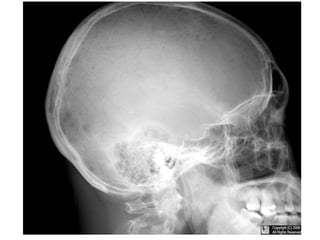

Punched Out” Skill Lesions

• Multiple Myeloma

• Langerhans Cell Histiocytosis

• Metastatic Carcinoma

• Neuroblastoma